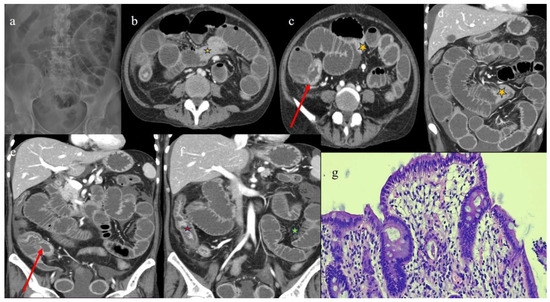

| 5 | P | P | Multisegmental thickness with stenosis on jejunal loops and SBO and segmental and focal thickness on the terminal ileus and appendix | Diffuse parietal thickness with stratified enhancement | Mild comb sign, poor reactive mesenteric lymph node, small air bubbles in the ascites | Small splenic areas of ischemia |